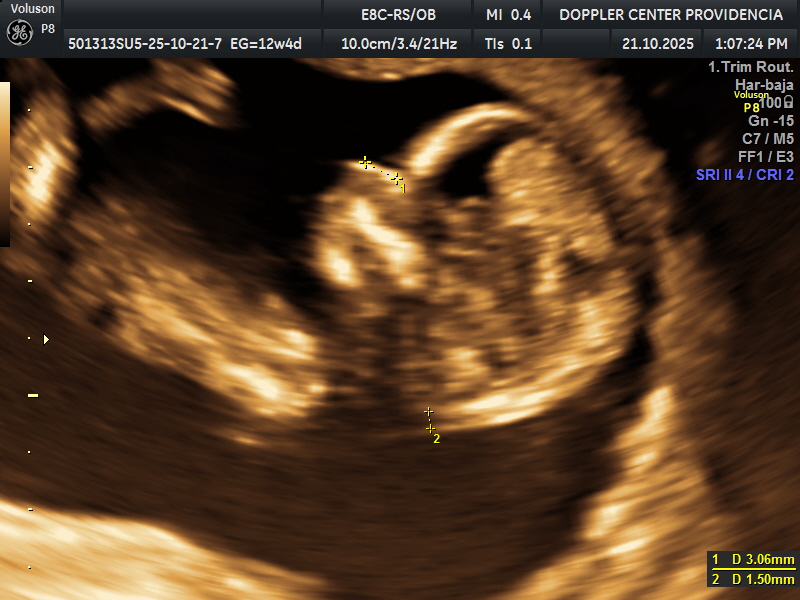

Es una técnica especializada de ultrasonido que utiliza el efecto Doppler para evaluar el flujo sanguíneo en el sistema circulatorio del feto y la madre durante el embarazo.

Se usa principalmente para evaluar el flujo sanguíneo en la placenta, el cordón umbilical y los vasos sanguíneos de la madre y el feto. Esto proporciona información valiosa sobre la salud del embarazo y la circulación fetal.

• Eco Doppler 11-14 semanas